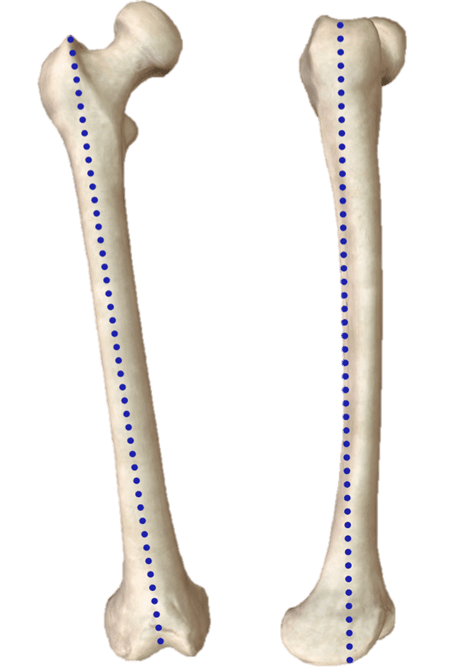

What blue line represent on this femur?

Anatomical Axis

The weight bearing axis also known as -------------------

Mechanical Axis